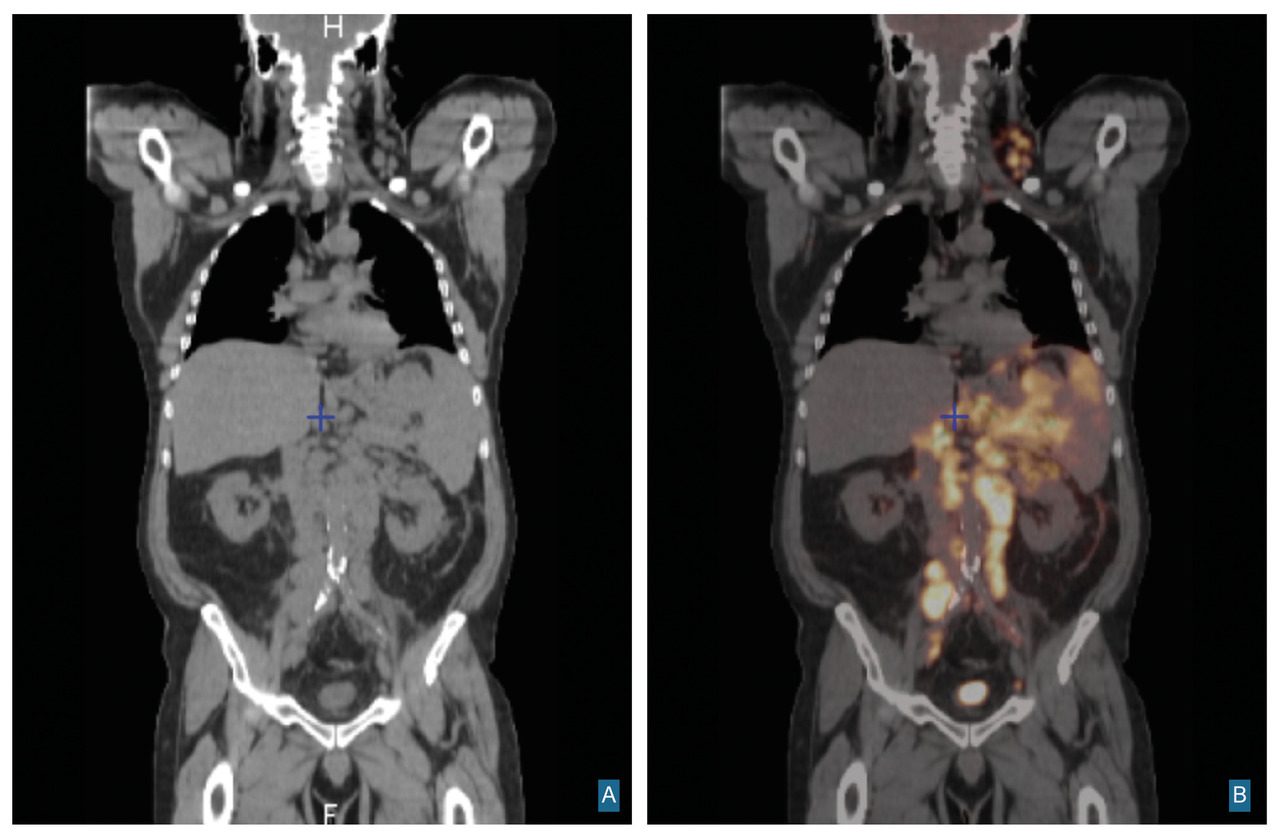

La tomographie à émission de positons ou TEP-scan est un examen scintigraphique fondé sur l’injection d’un radiotraceur (18-fluorodéoxyglucose [18-FDG]) contenant du glucose (et non de l’iode), émetteur de positons ; c’est une imagerie fonctionnelle qui se superpose à l’imagerie anatomique donnée par le scanner. Le diabète ne constitue pas une contre-indication mais doit être équilibré au moment de l’examen pour une interprétation fiable des images. De même, les perfusions de glucose sont prohibées douze heures avant l’examen.

Le TEP-scan permet de détecter des atteintes non visibles en imagerie conventionnelle : atteinte de l’os, de la moelle osseuse, d'autres organes extralymphatiques. Son niveau de résolution est de 5 à 10 mm. L’avidité des cellules pour le glucose marqué varie en fonction du type histologique et du nombre de cellules en cycle (indice mitotique).

Cet examen est utile dans le suivi des patients sous traitement et permet de faire la distinction entre une masse résiduelle non active et une maladie résiduelle active. Il peut également identifier une atteinte médullaire. Des phénomènes inflammatoires (infections) peuvent être à l’origine de faux positifs. Les frissons, le stress peuvent également conduire à modifier la distribution du glucose vers des régions riches en graisse brune (cou). L’utilisation de bêtabloquants avant l’examen peut limiter ce phénomène.